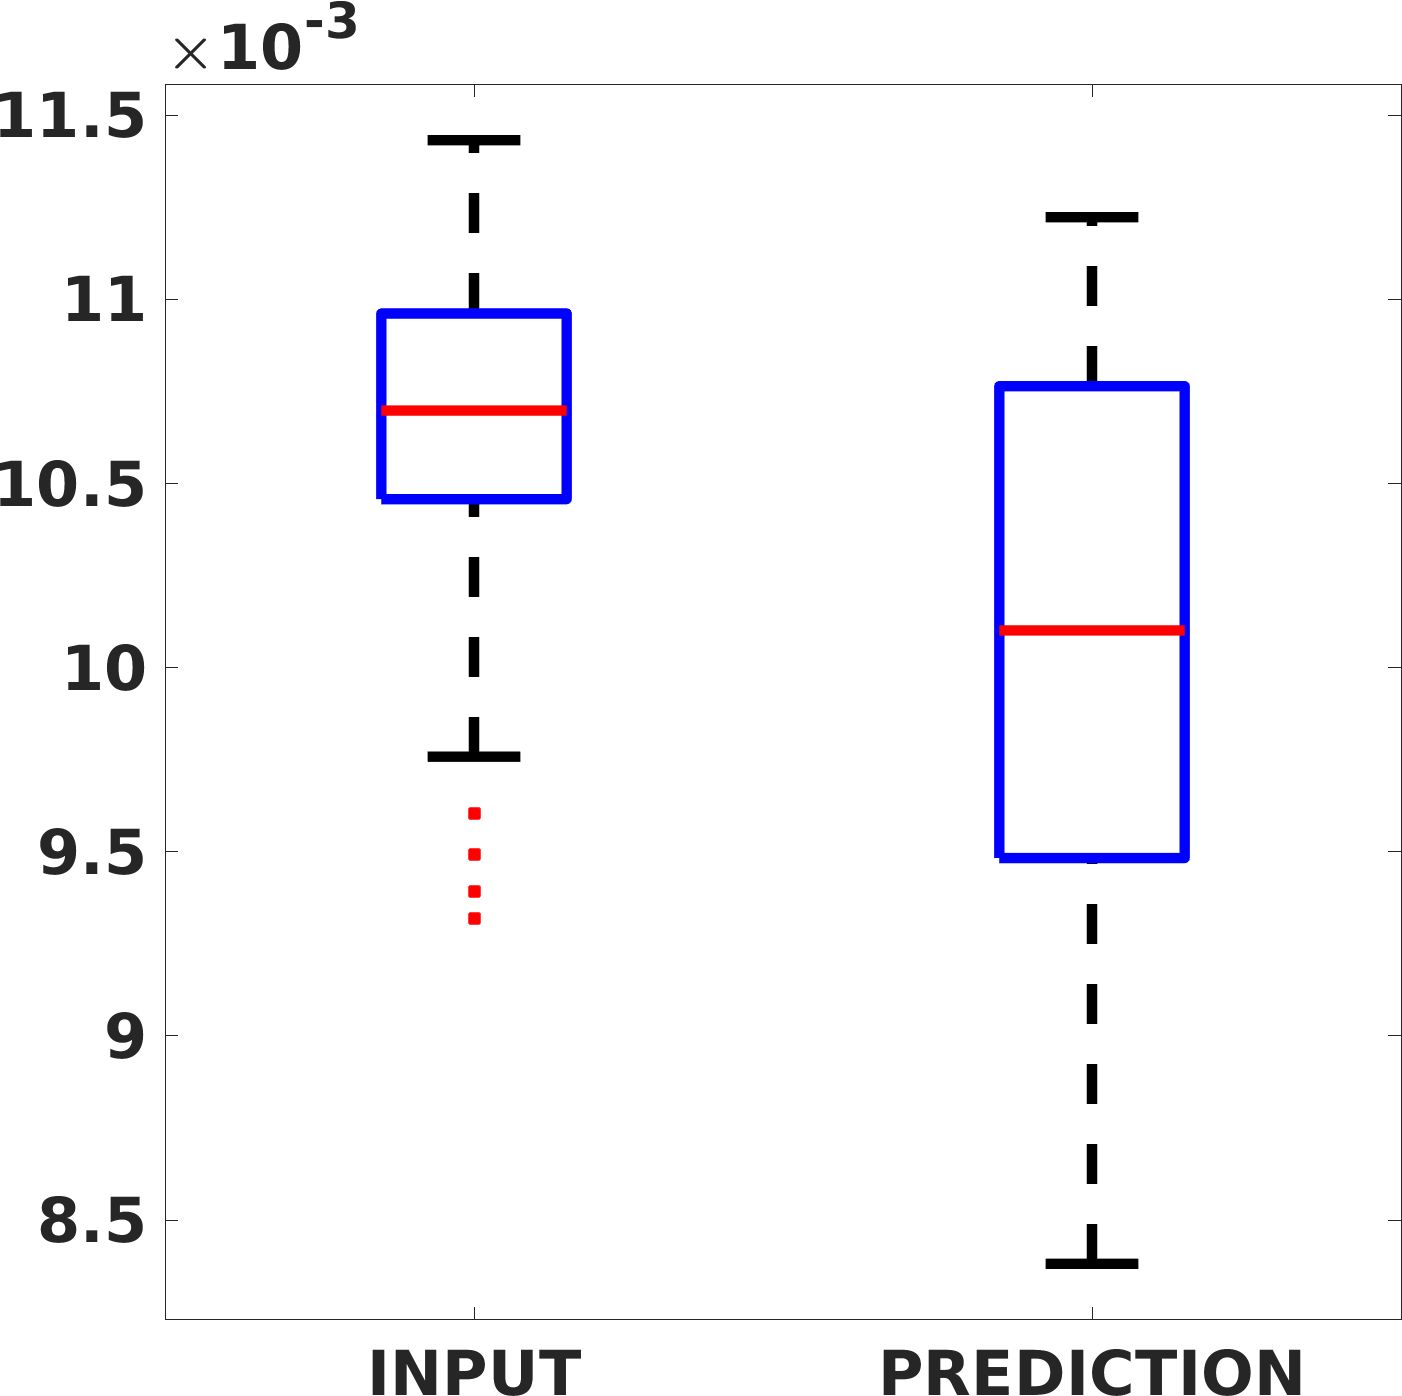

Fig. 7(a-b-c, left) shows the box plot of the statistics of the PSNR on three different anatomical districts, comparing the target images with the prediction and the cubic convolution, respectively. The metrics are computed on a data set of 200 images of the same district and with the same up-sampling factor. We report that the PSNR median value improves of on obstetric 2X raw images, on cardiac 2X raw images, and on abdominal raw 4X images.

Fig. 7(a-b-c, right) shows the histogram of the absolute value of the error with respect to the target image, of the prediction and Cubic convolution results, respectively. The histograms show the number of pixels where the prediction error is lower than 5 (i.e., the first bin of the histogram), which means very similar to the target when visually analysing the images. From the Cubic convolution to the predicted images, this value increases of on obstetric 4X raw images, on cardiac 4X raw images, and on abdominal 4X raw images.

Fig. 8 shows the box plot of the SSIM (a-b-c, left) and MAE (a-b-c, right) quantitative metrics, as performed for PSNR metric. Also, these metrics show that our method improves the results of Cubic convolution both in terms of average value and variability. For example, the SSIM median value improves of on obstetric 4X images and the MAE median value improves of on cardiac 2X images.